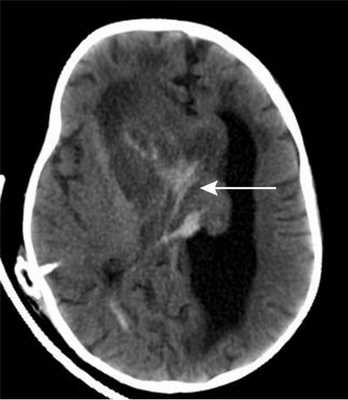

По месту жительства ребенку был установлен вентрикулоперитонеальный шунт, на фоне которого состояние несколько улучшилось — стала активней, аппетит улучшился. При поступлении в Институт нейрохирургии у ребенка развились клонические судороги в левых конечностях с поворотом головы и глаз влево. КТ головного мозга показало наличие свежей крови в строме опухоли, что было расценено, как кровоизлияние в опухоль (рис. 2).

![]()

Рисунок 2. Компьютерная томограмма головного мозга грудного ребенка 11 мес с гигантской внутрижелудочковой опухолью. Кровоизлияние в строму опухоли.